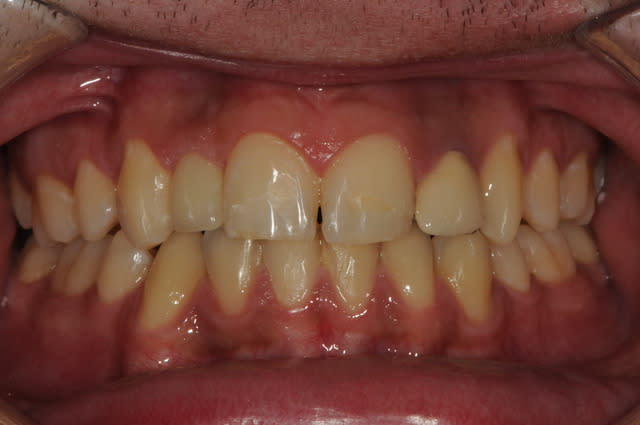

photos finish!!!

à noter...avec le flash...difficile de rendre le "naturel" de ces restaurations(teintes très claires)...après petite gingivoplastie pour harmoniser la hauteur des collets...(surtout pour 12...)